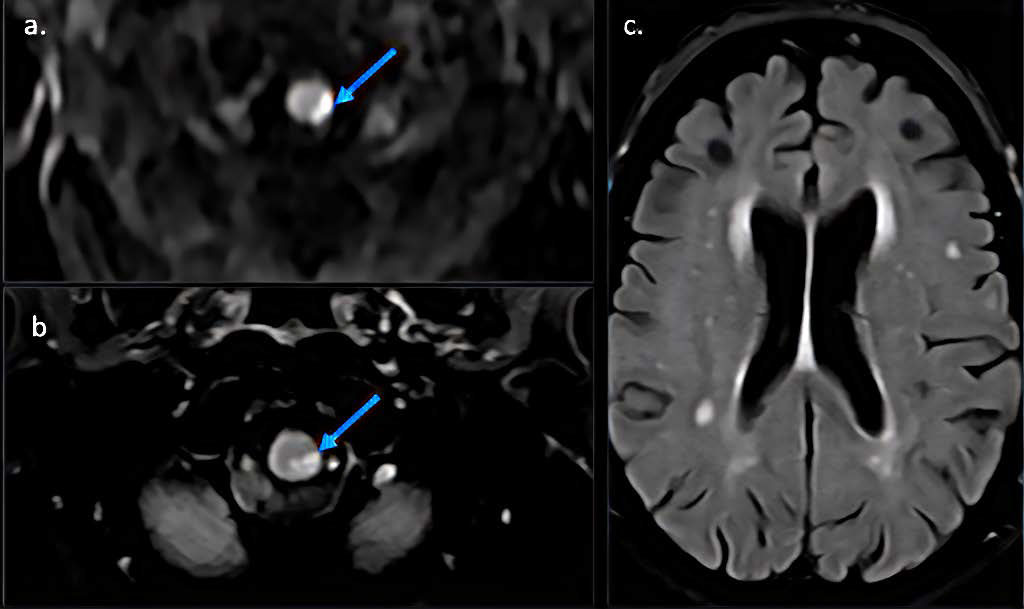

A Case of Listeria Rhomboencephalitis with Misleading Imaging Presentation and Laboratory Findings

Adrien De Minteguiaga, Anna Paola Bocchio, MD, Valeria Onofrj, MD